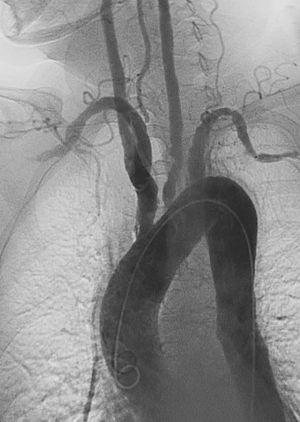

Left anterior oblique angiographic image of Takayasu's arteritis showing areas of stenosis in multiple great vessels

Contrast angiography has been the gold standard. The earliest detectable lesion is a local narrowing or irregularity of the lumen. This may develop into stenosis and occlusion. The characteristic finding is the presence of "skip lesions," where stenosis or aneurysms alternate with normal vessels. Angiography provides information on vessel anatomy and patency but does not provide information on the degree of inflammation in the wall.[11]